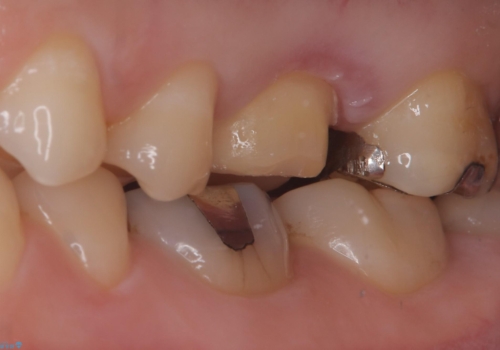

保険のメタルインレーを白くしたいということで来院されました。

左上6の近心にカリエスを認め、残存歯質と破折リスクの観点からセラミッククラウンでのやり替えとなりました。

今後ホワイトニング行う予定のため、シェード明るめにしています。